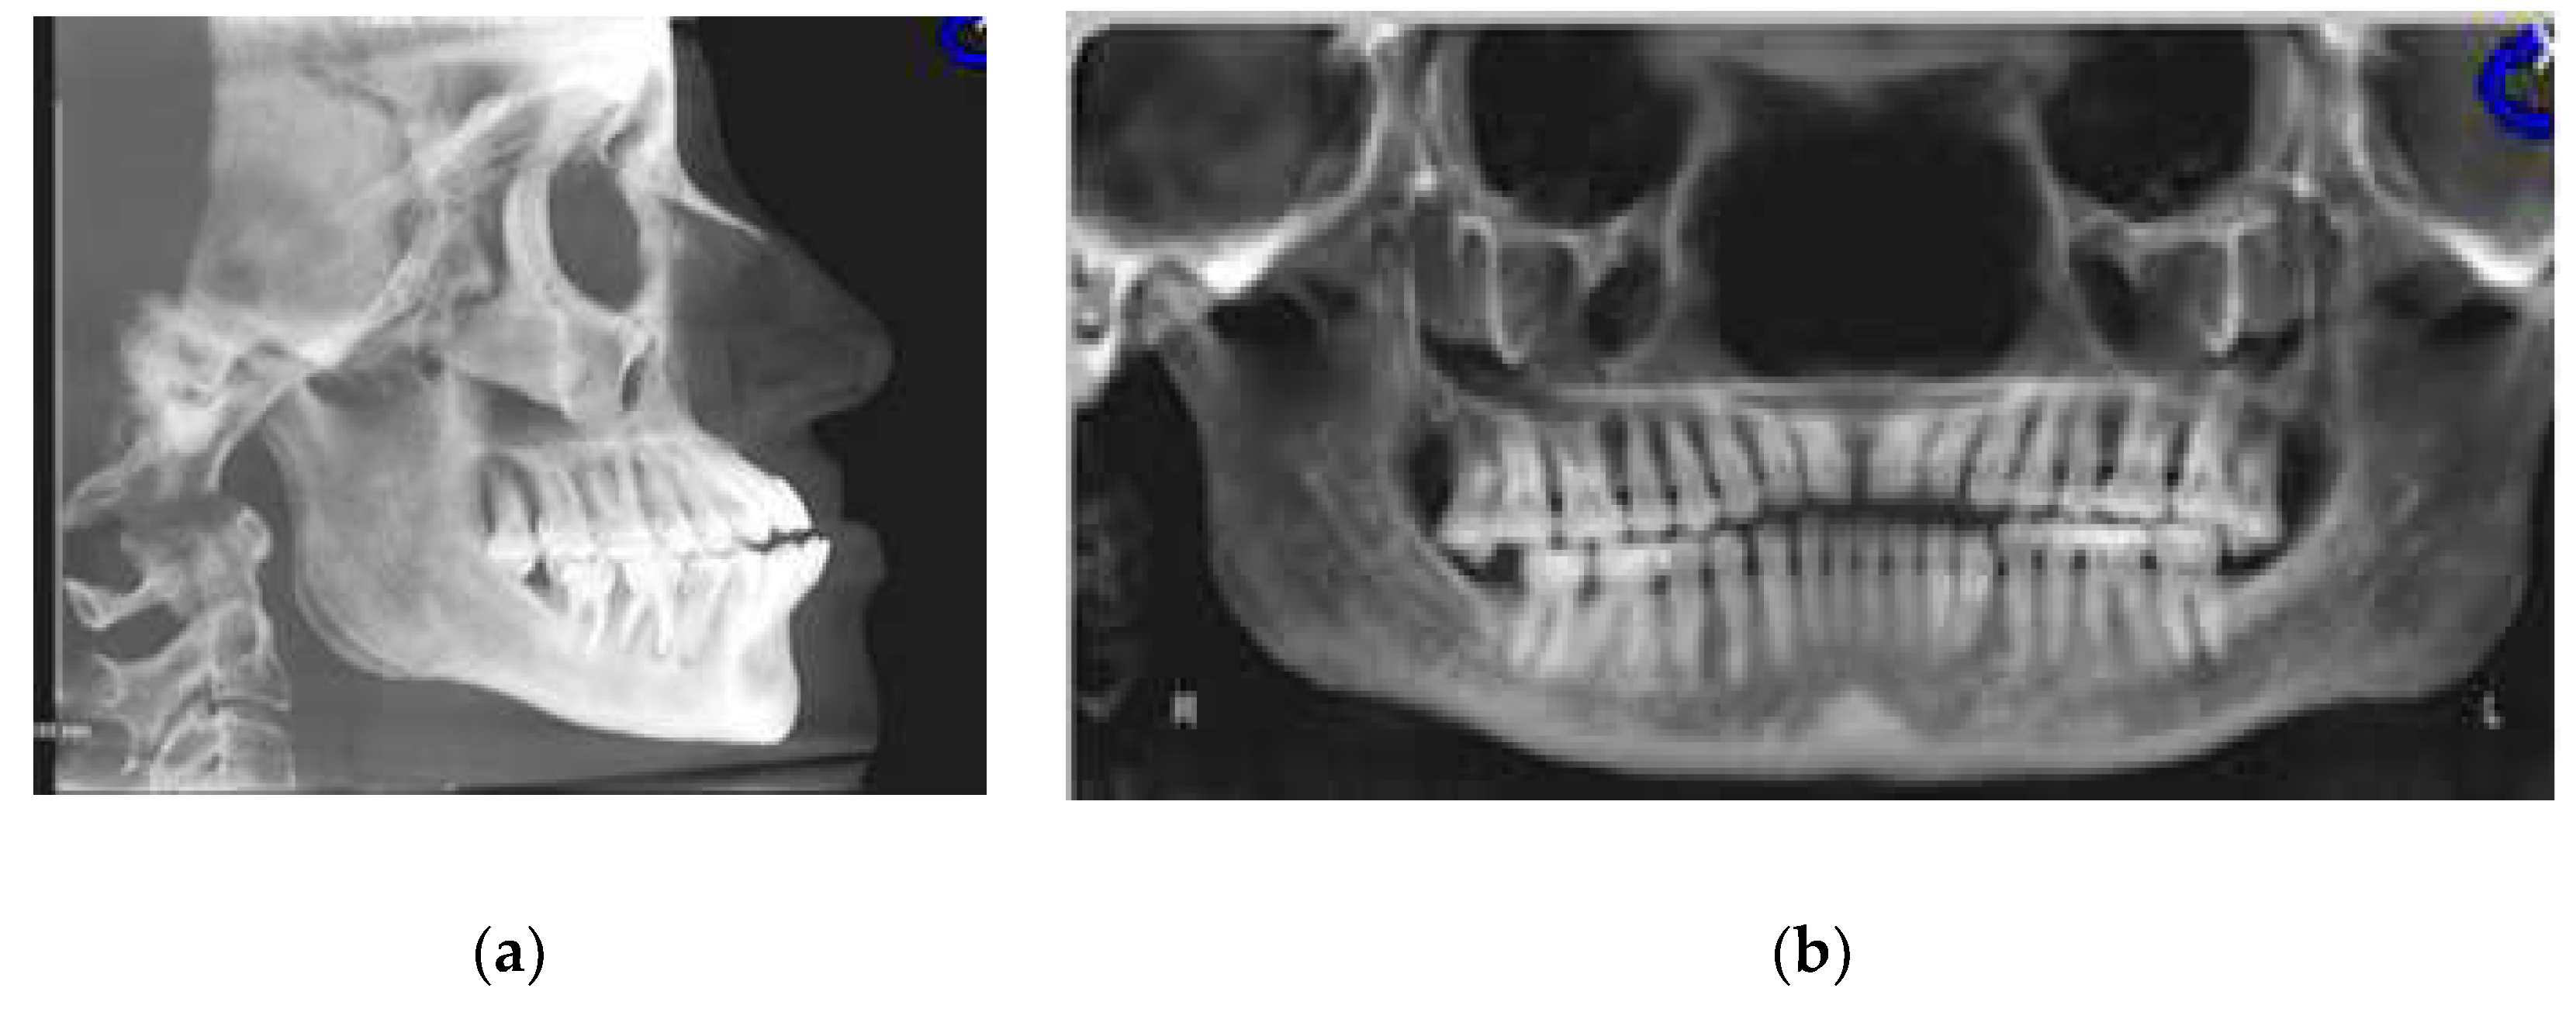

3.2. CBCT-Driven Radiographs

3.2.1. Cephalometric Radiographs and Analysis

3.2.2. Panoramic and Sagittal Screen Radiographs